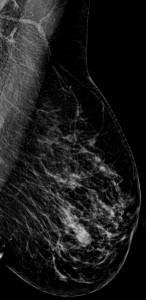

Caso 04

María Esther Estornell Cánovas